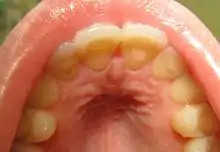

Loss of enamel (acid erosion) from the inside of the upper front teeth as a result of bulimia

People with bulimia are at a higher risk to have an affective disorder, such as depression or general anxiety disorder. One study found 70% had depression at some time in their lives (as opposed to 26% for adult females in the general population), rising to 88% for all affective disorders combined.[27] Another study in the Journal of Affective Disorders found that of the population of patients that were diagnosed with an eating disorder according to the DSM-V guidelines about 27% also suffered from bipolar disorder. Within this article, the majority of the patients were diagnosed with bulimia nervosa, the second most common condition reported was binge-eating disorder.[28] Some individuals with anorexia nervosa exhibit episodes of bulimic tendencies through purging (either through self-induced vomiting or laxatives) as a way to quickly remove food in their system.[29] There may be an increased risk for diabetes mellitus type 2.[30] Bulimia also has negative effects on a person's teeth due to the acid passed through the mouth from frequent vomiting causing acid erosion, mainly on the posterior dental surface.